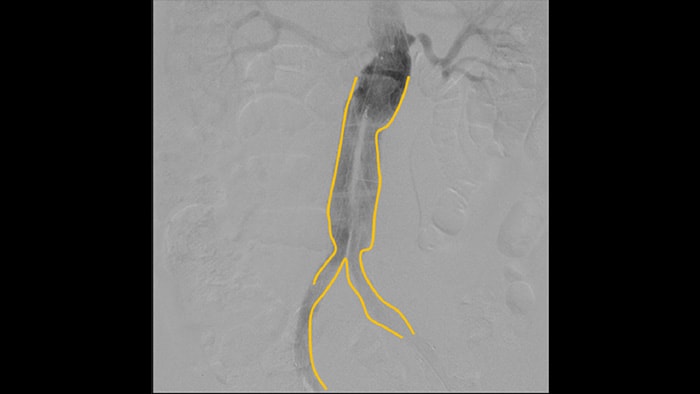

Цифровая субтракционная ангиография (DSA) используется в интервенционных сосудистых процедурах для четкой визуализации кровеносных сосудов путем удаления структур, которые могут снижать видимость сосудов. В рамках рентгеноскопии с картой сосудов ранее полученное субтракционное изображение с контрастированием накладывается на полученное рентгеноскопическое изображение в режиме реального времени, что позволяет отслеживать устройство без повторного введения контраста.

Используйте инструмент для контуринга, чтобы с легкостью отметить бифуркацию или боковые ответвления, рисуя на мониторе передвижной станции просмотра пальцем или подключенной к устройству мышью.